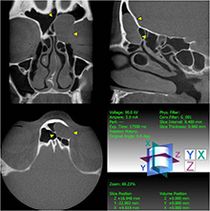

Dentogene Sinusitis der Kieferhöhle links durch eine Entzündung im Bereich einer Zahnwurzelspitze mit Zerstörung des umgebenden knöchernen Kieferhöhlenbodens (Digitale Volumentomographie, DVT)

Die Diagnostik dieser Erkrankung basiert neben der Beschwerdesymptomatik (Nasenatmungsbehinderung, Schmerzen/Druck, Sekretion, Riechminderung) auf der Endoskopie der Nase und der obligaten Schnittbilddiagnostik der Nasennebenhöhlen. Hierzu verfügen wir über die derzeit modernste Diagnostik – die Digitale Volumentomographie (DVT) –, die eine hochauflösende dreidimensionale Darstellung des Geschichtsschädels, der Nasennebenhöhlen und des Oberkiefers bei im Vergleich zur konventionellen Computertomographie deutlich niedrigerer Strahlenbelastung ermöglicht.